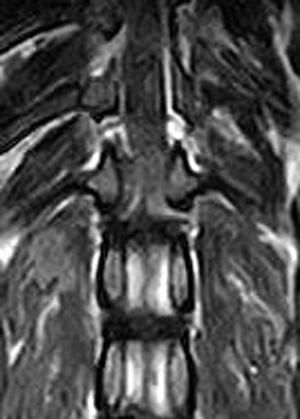

市外の先生からフレブルちゃん両後肢麻痺グレード3でMRI検査及び手術依頼でご紹介がありました。MRI検査で第12‐13胸椎間椎間椎間板ヘルニア、右側優位な圧迫と診断し手術となりました。